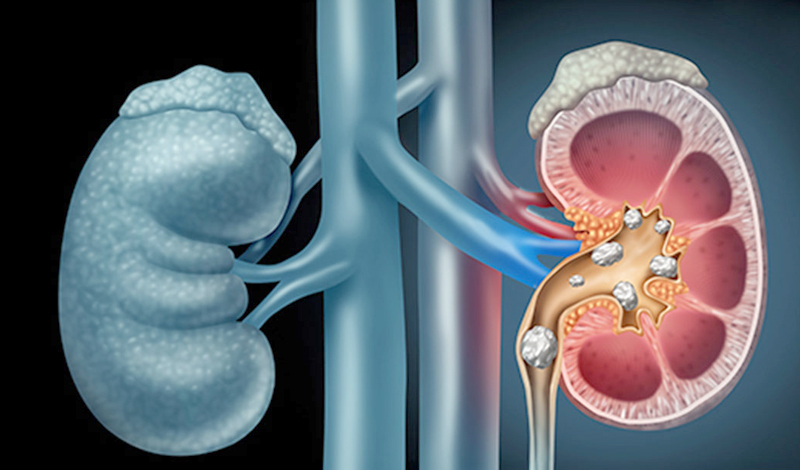

Kidney Stone Disease

Kidney Stone Disease occurs when hard mineral and salt deposits form inside the kidneys due to